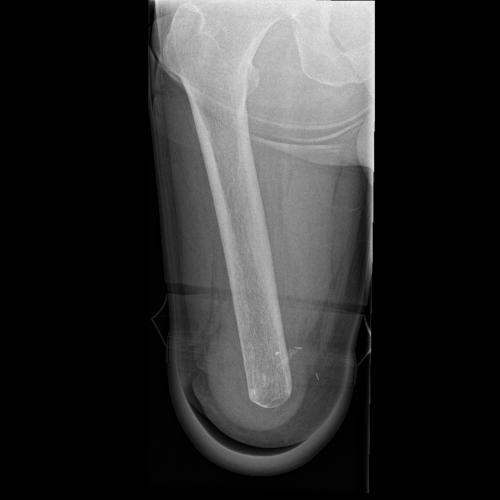

image of after osseointegration

After Osseointegration

The implant penetrates through the skin, allowing attachment of an artificial limb to the human skeleton via a connector.

Osseointegration is a procedure in which a titanium implant is surgically inserted into the bone to provide a stable anchor for prosthetic limbs. The implant fuses with the bone over time, bypassing the need for traditional socket-based fittings.